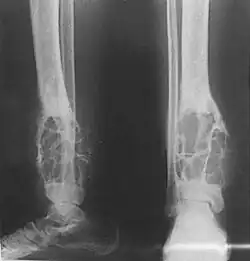

Radiograph showing an adamantinoma in the distal tibia with lytic expansive changes.

X-rays of the affected area show a well defined tumour in bone, with multiple lobules giving a "soap bubble" appearance.[9] MRI can provide a more useful guide to its severity.[9]